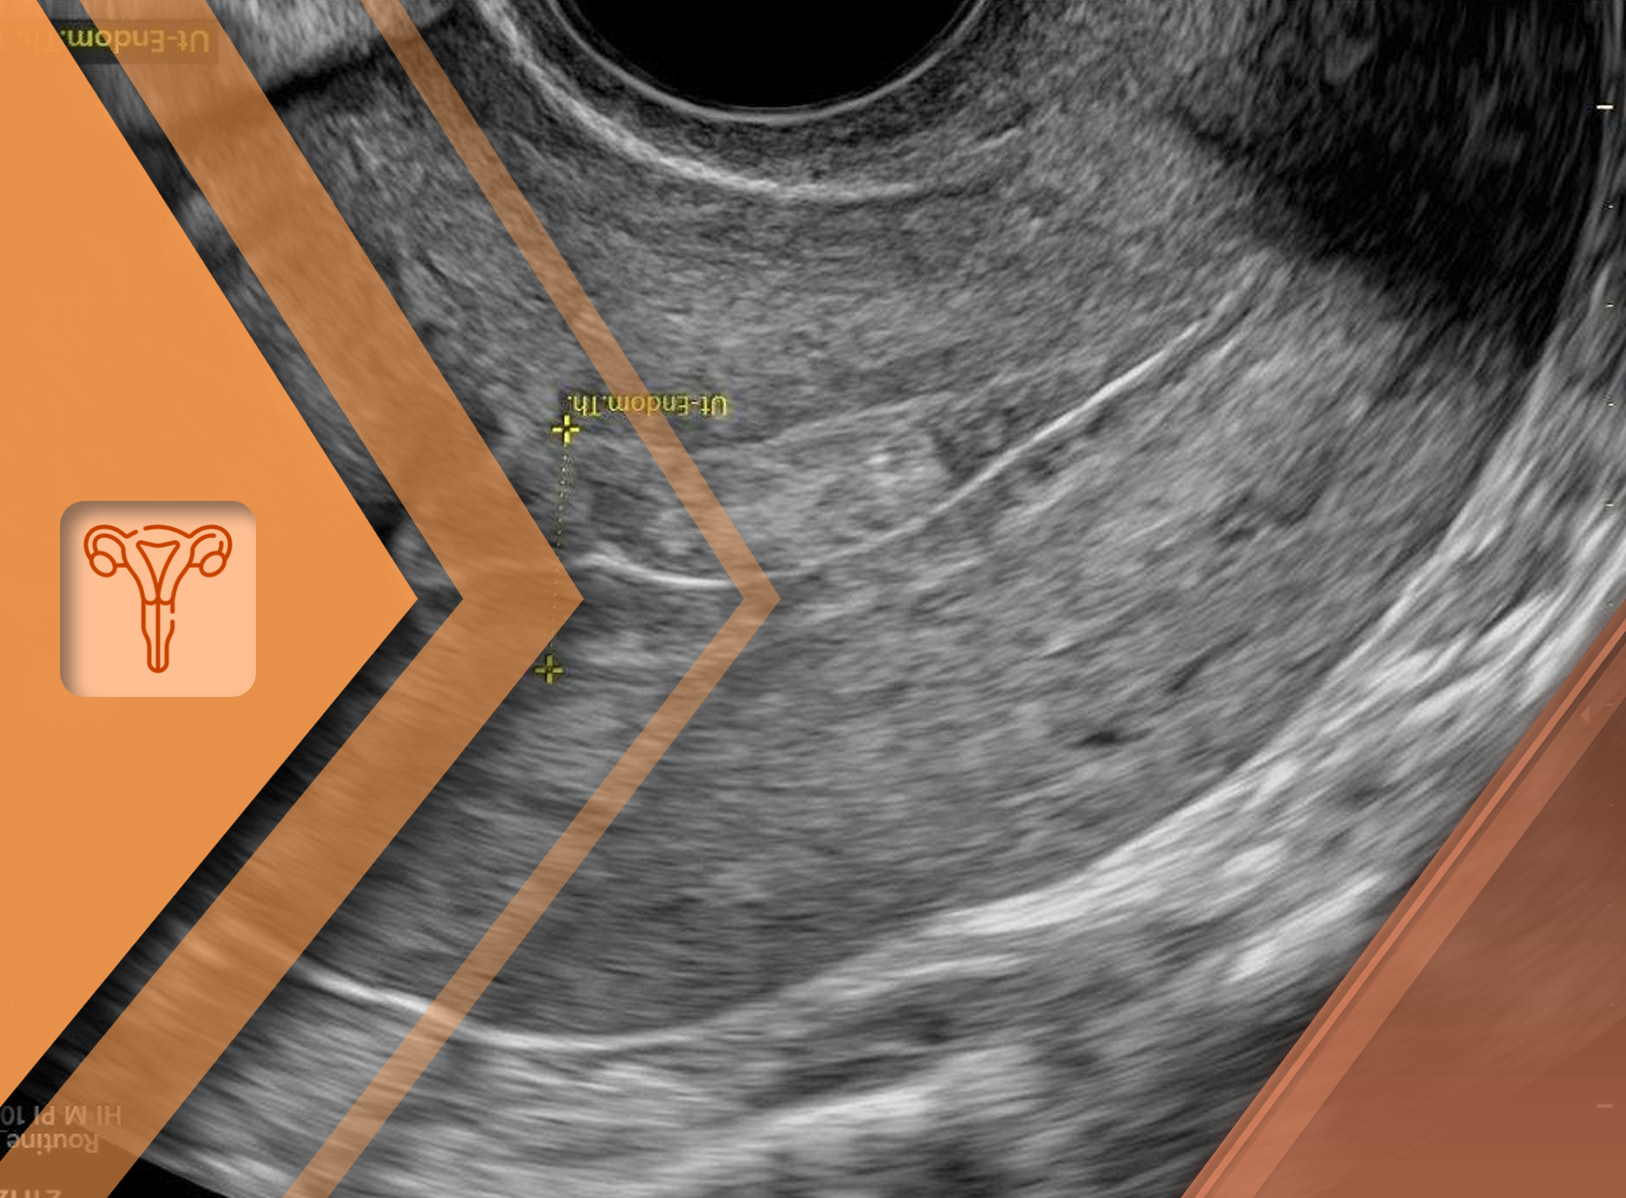

Sangramento pós-menopausa: Investigação e diagnóstico